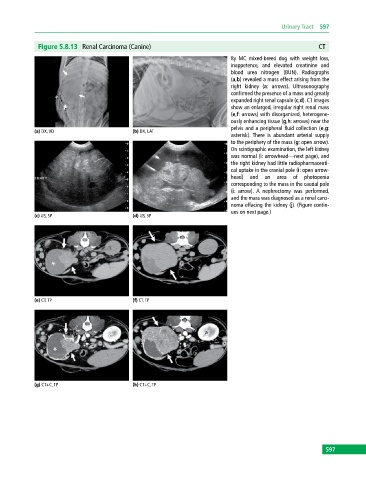

Figure 5.8.13 Renal Carcinoma (Canine) CT

8y MC mixed‐breed dog with weight loss,

inappetence, and elevated creatinine and

blood urea nitrogen (BUN). Radiographs

(a,b) revealed a mass effect arising from the

right kidney (a: arrows). Ultrasonography

confirmed the presence of a mass and greatly

expanded right renal capsule (c,d). CT images

show an enlarged, irregular right renal mass

(e,f: arrows) with disorganized, heterogene-

ously enhancing tissue (g,h: arrows) near the

pelvis and a peripheral fluid collection (e,g:

(a) DX, VD (b) DX, LAT

asterisk). There is abundant arterial supply

to the periphery of the mass (g: open arrow).

On scintigraphic examination, the left kidney

was normal (i: arrowhead—next page), and

the right kidney had little radiopharmaceuti-

cal uptake in the cranial pole (i: open arrow-

head) and an area of photopenia

corresponding to the mass in the caudal pole

(i: arrow). A nephrectomy was performed,

and the mass was diagnosed as a renal carci-

noma effacing the kidney (j). (Figure contin-

ues on next page.)

(c) US, SP (d) US, SP

(e) CT, TP (f) CT, TP

(g) CT+C, TP (h) CT+C, TP